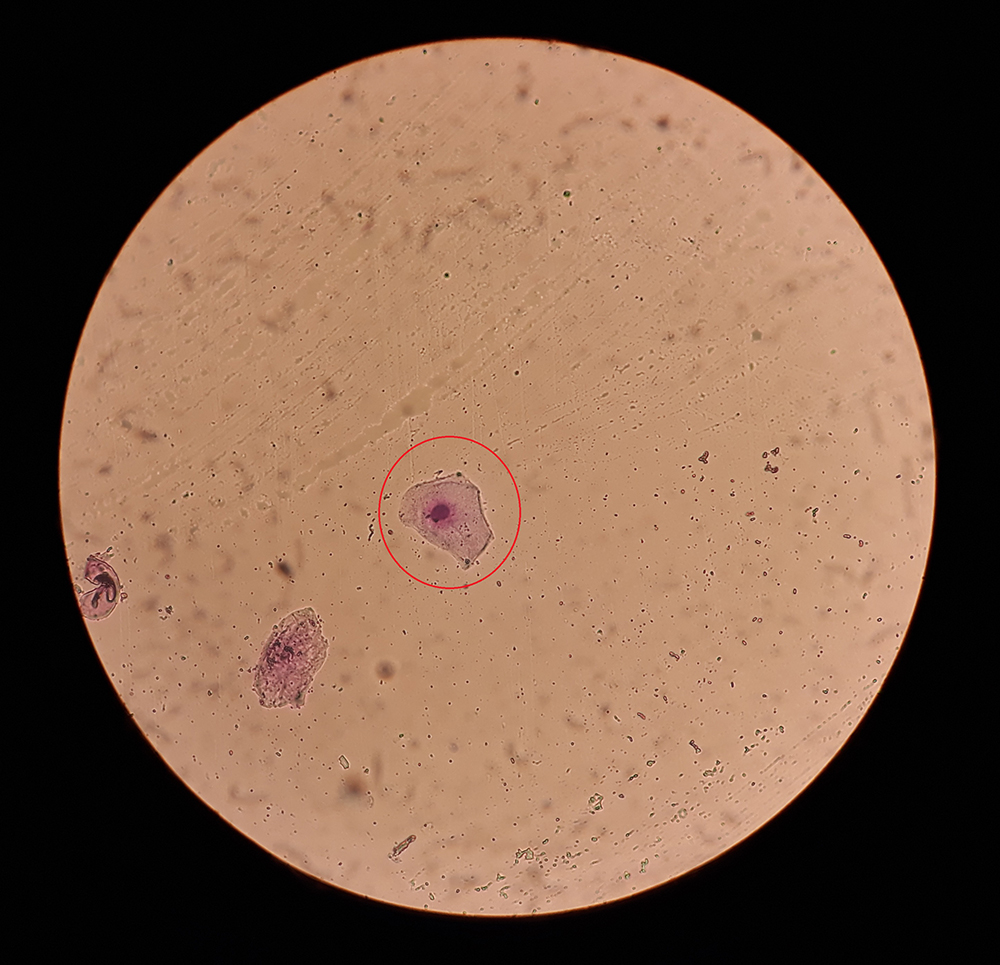

Cytologie

Bij cytologie wordt een afdrukpreparaatje gemaakt van het slijmvlies van de vulva. Dit betekent dat een microscoopglaasje kort tegen het slijmvlies van de vulva gedrukt wordt, waardoor er celletjes worden afgegeven. Deze kunnen vervolgens, na kleuring, onder de microscoop worden bekeken. Dit wordt gedaan door dierenarts A. Rappoldt.

Het type cellen dat in het preparaat aanwezig is, vertelt iets over in welk stadium van haar cyclus de teef verkeert.